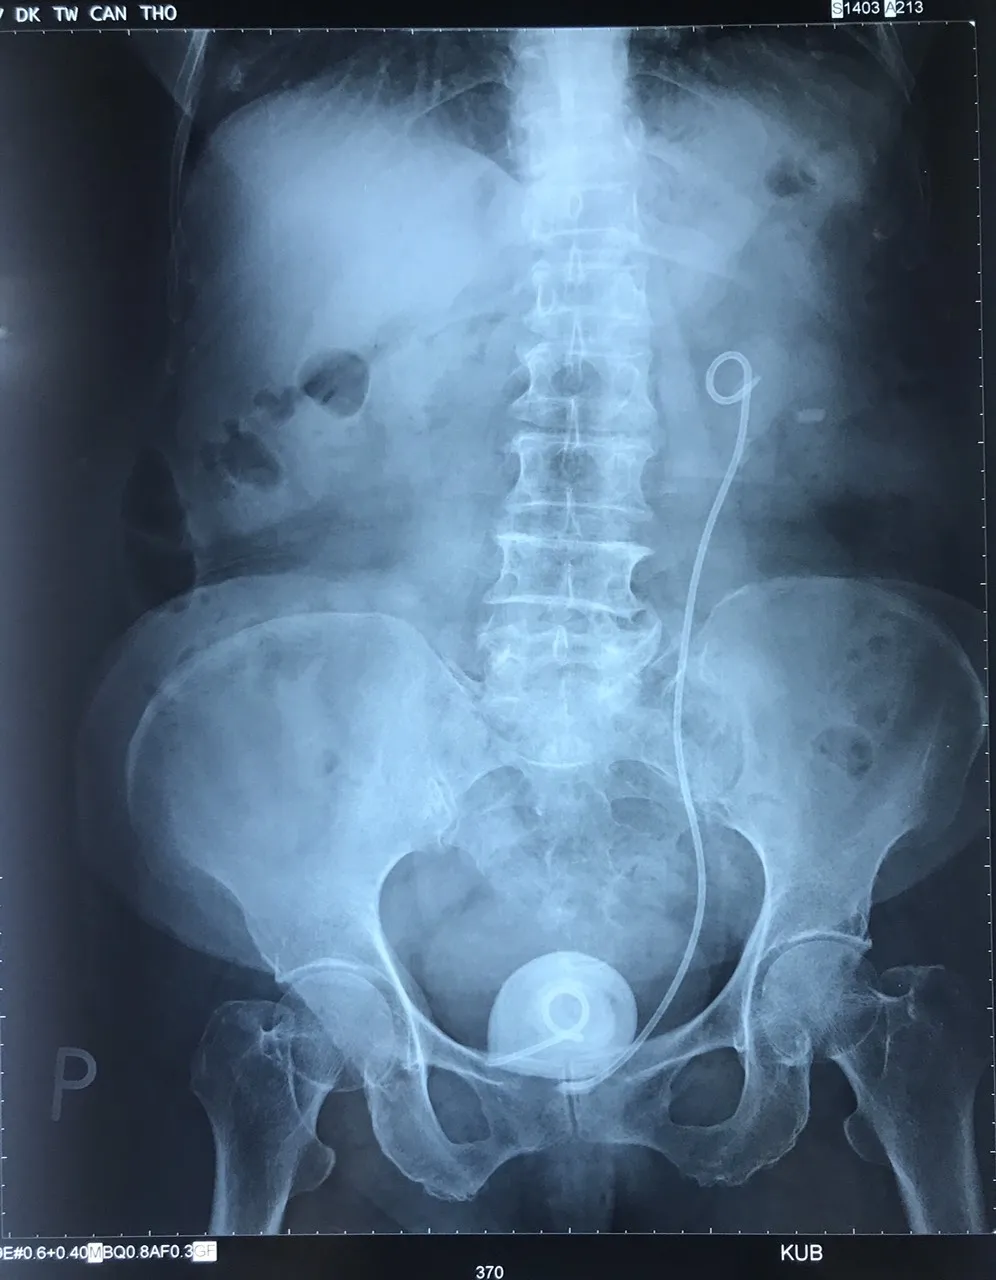

Tại Bệnh viện Đa khoa Trung ương Cần Thơ, sau khi chụp cắt lớp vi tính hệ tiết niệu, các bác sĩ xác định trong cơ thể cụ bà còn ống thông bị đứt đoạn ở vị trí  bàng quang tạo thành sỏi to. Phần đầu trên ống có sỏi nhỏ bám.

Các bác sĩ đã phẫu thuật lấy thành công viên sỏi bàng quang lớn bằng quả trứng, kích thước 5 x 4 x 5 cm có đầu ống thông bên trong, đồng thời rút thành công ống thông.

Viên sỏi bàng quang lớn bằng quả trứng và ống thông trên phim chụp X-quang. Ảnh: Hải Dương